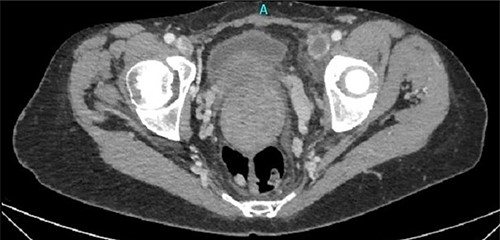

The macroscopic description reported a large compact solid mass with oblique perimeter with dimensions of 27 × 18 × 15.5 cm (Fig. 4). The microscopic examination reported a leiomyoma of uterus with vitreous degeneration, with mild to moderate lesions of cervicitis.